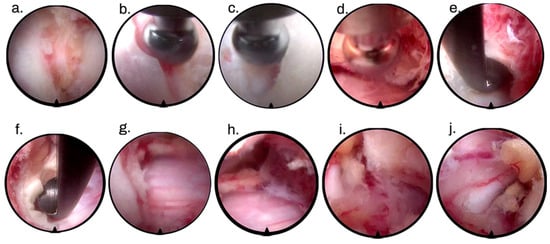

2. Surgical Technique